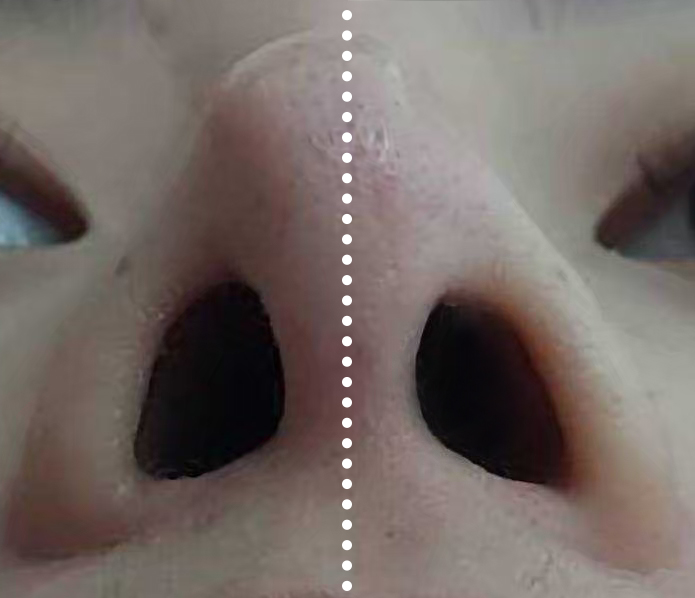

1 ตรวจการเบี้ยวเอียง ปัญหาใหญ่ของการเสริมจมูก ไม่ว่าจะเป็นแบบ openหรือ closed rhinoplasty ก็คือ การเอียง,เบี้ยว คำตอบของผู้ให้กับผู้รับบริการ ที่ไม่ตรงกัน เรามีคำตอบและพิสูจน์ได้ด้วยตาคุณเอง 100% ไม่ว่าจะเป็นที่ไหน โคนหรือปลายจมูก? มากหรือน้อย?

ในกรณีเอียงไม่มาก อาจเป็นสาเหตุให้แกนจมูกใหญ่ หรือ รูจมูกไม่เท่ากันได้ เราสามารถตรวจได้อย่างมั่นใจจากการเห็นภายใน โดยไม่ขึ้นกับอาการบวม เหมือนการตรวจด้วยการมองหรือการคลำ